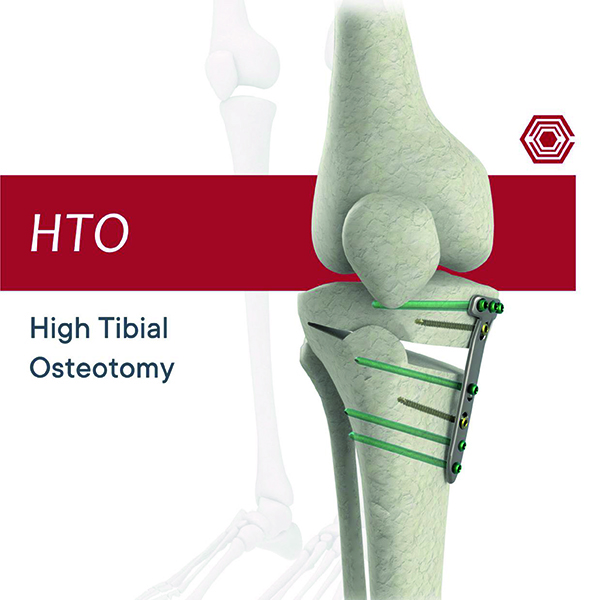

High Tibial Osteotomy

Akif Kaya Aybek

Norm Akademi

- Surgical Technique

- Implant Types

- Instrument Container

- Instrument Types